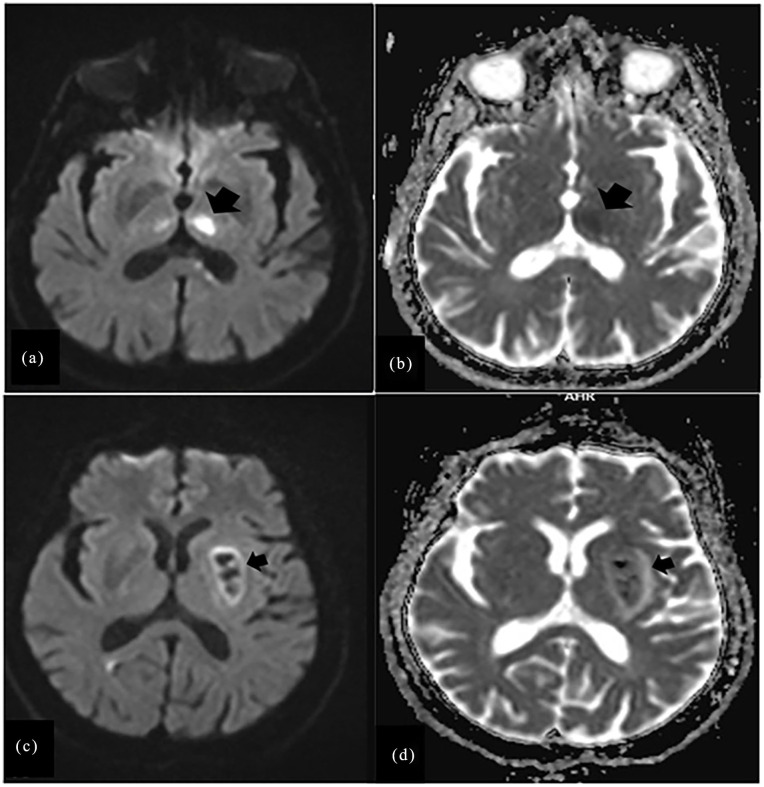

Results: Restless legs syndrome was diagnosed in 59 patients (11.6%), including 37 (13.1%) who had ischemic stroke and 12 (8.6%) who had hemorrhagic stroke. An increased rate of restless legs syndrome was observed in stroke patients with brain lesions in the thalamus and lentiform nucleus; those who smoked; and those with a family history of restless legs syndrome.

Conclusions: This study found that the incidence of restless legs syndrome after stroke was 11.6% overall and 13.1% and 8.6% after ischemic and hemorrhagic strokes, respectively. Lesion in the thalamus and lentiform nucleus, smoking history, and family history of restless legs syndrome were the predictors of restless legs syndrome after stroke onset.